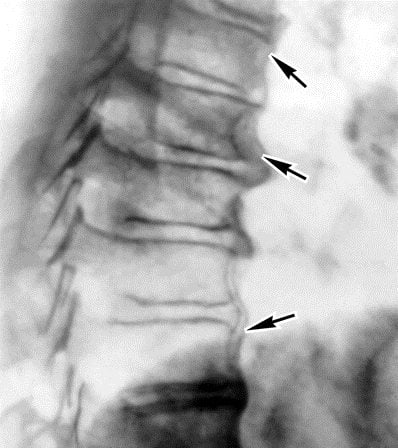

Диагностику болей позвоночника в середине спины начинают с общего осмотра и сбора анамнеза. После этого специалист назначает необходимые исследования. На начальном этапе диагностики обычно ограничиваются рентгеном и общими анализами крови и мочи.

В дальнейшем могут потребоваться следующие исследования:

- биохимический анализ крови;

- ультразвуковое сканирование;

- магнитно-резонансная томография;

- компьютерная томография;